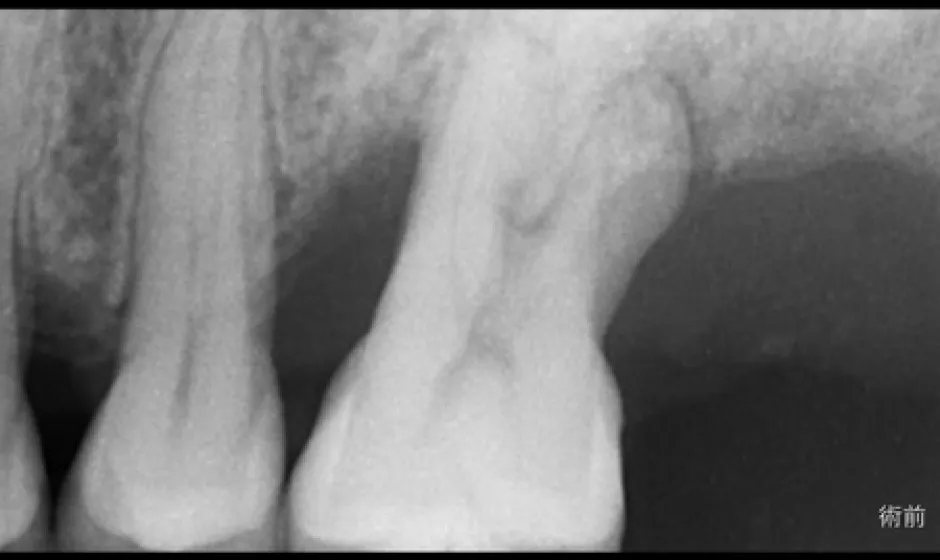

症例2

- 治療名

- マイクロスコープとラバーダムを使用した精密根管治療

- 患者様

- 40代女性

- 執刀医

- Dr. 大杉

- 治療期間

- 3ヶ月

- 治療費

- 精密根管治療:130,000円(税込)

築造:40,000円(税込)

セラミック:130,000円(税込) - リスク

- 治療中〜治療後に痛みが出る場合あり

再感染・治癒不全の可能性

補綴後も定期管理が必要